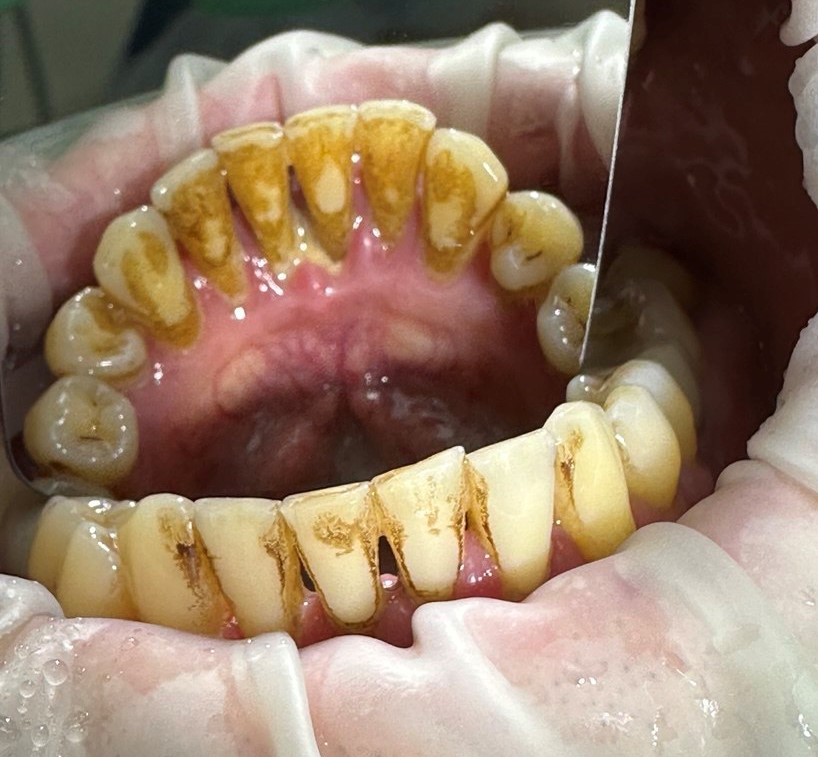

Проблема

Пациент обратился с проблемой зубного налета и образование зубного камня на верхних и нижних передних зубах, неприятный запах изо рта, покраснения и болезненные ощущения на деснах.

Решение

Проведена профессиональная гигиена полости рта (AirFlow). Удален зубной камень и налет. Проведено воздействие ультразвуком на область дёсен аппаратом Vector, обе челюсти.